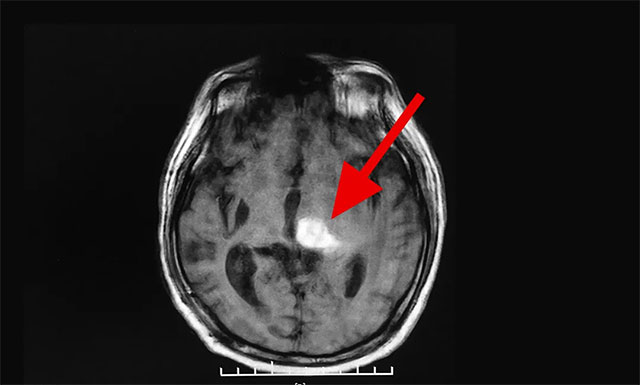

“这是我老伴第二次脑出血了,当时就诊的医生就告诉我说,这次他脑出血很严重,虽然他脑出血量不是很大,但出血点比较多,部位也很关键。”刘女士回忆道,根据病历上反映:患者张先生是左侧基底节区脑出血,并破入脑室,同时双侧基底节及半卵圆区多发腔隙性脑梗死。“医生让我们家属做好心理准备,即使保住了性命,可能也要长期偏瘫在床了”,刘女士如是说。

▲ 患者脑出血比较严重,仍然处于昏迷状态

入院后,完善患者各项检查,戴秀珍主任对其进行了认真而全面的身体检查,发现患者右侧瞳孔对光反射迟钝; 不能言语,定向力、计算力、记忆力基本丧失; 右侧肢体肌力为0级,左侧肢体肌力为3级,四肢肌张力都比较高。